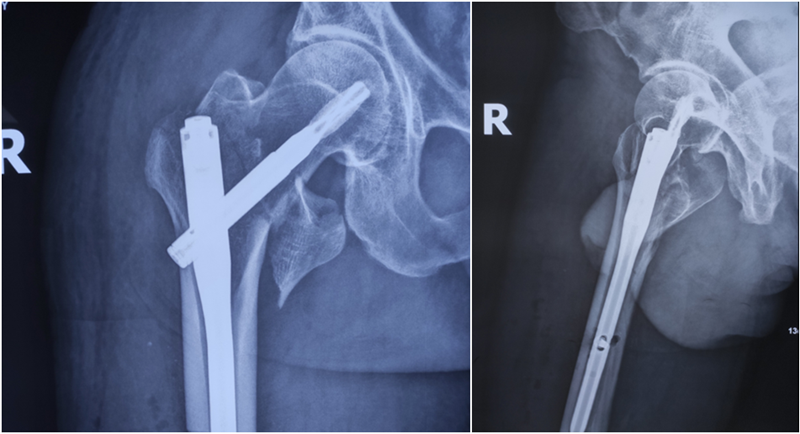

Xxx,男,71岁,右股粗隆间骨折3天,Evans-Jensen分型V型4分骨折块骨折;2020.2.28手术。

图18、图19